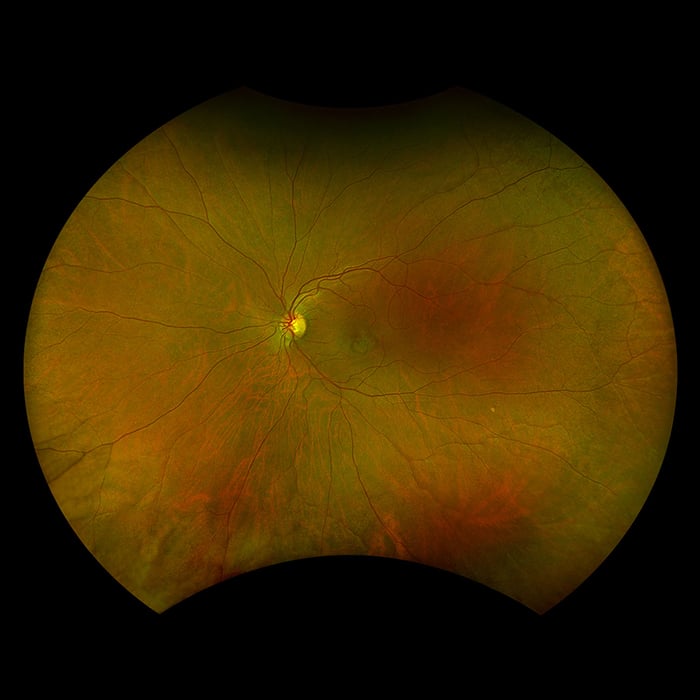

Ultra-widefield Scanning laser ophthalmoscopy (SLO) is a method of examination of the eye. It uses the technique of confocal laser scanning microscopy for diagnostic imaging of the retina. The digital high-definition view of the patient’s retina is called an optomap. The optomap image allows viewing of up to 200 internal degrees of the fundus in one image. It is used as a screening tool for early detection of disease or abnormalities in the posterior segment of the eye in the context of preventative medicine and eye health and wellness. As a digital image, an optomap can be used to educate the patient, saved to compare from year to year or used in telemedicine applications.